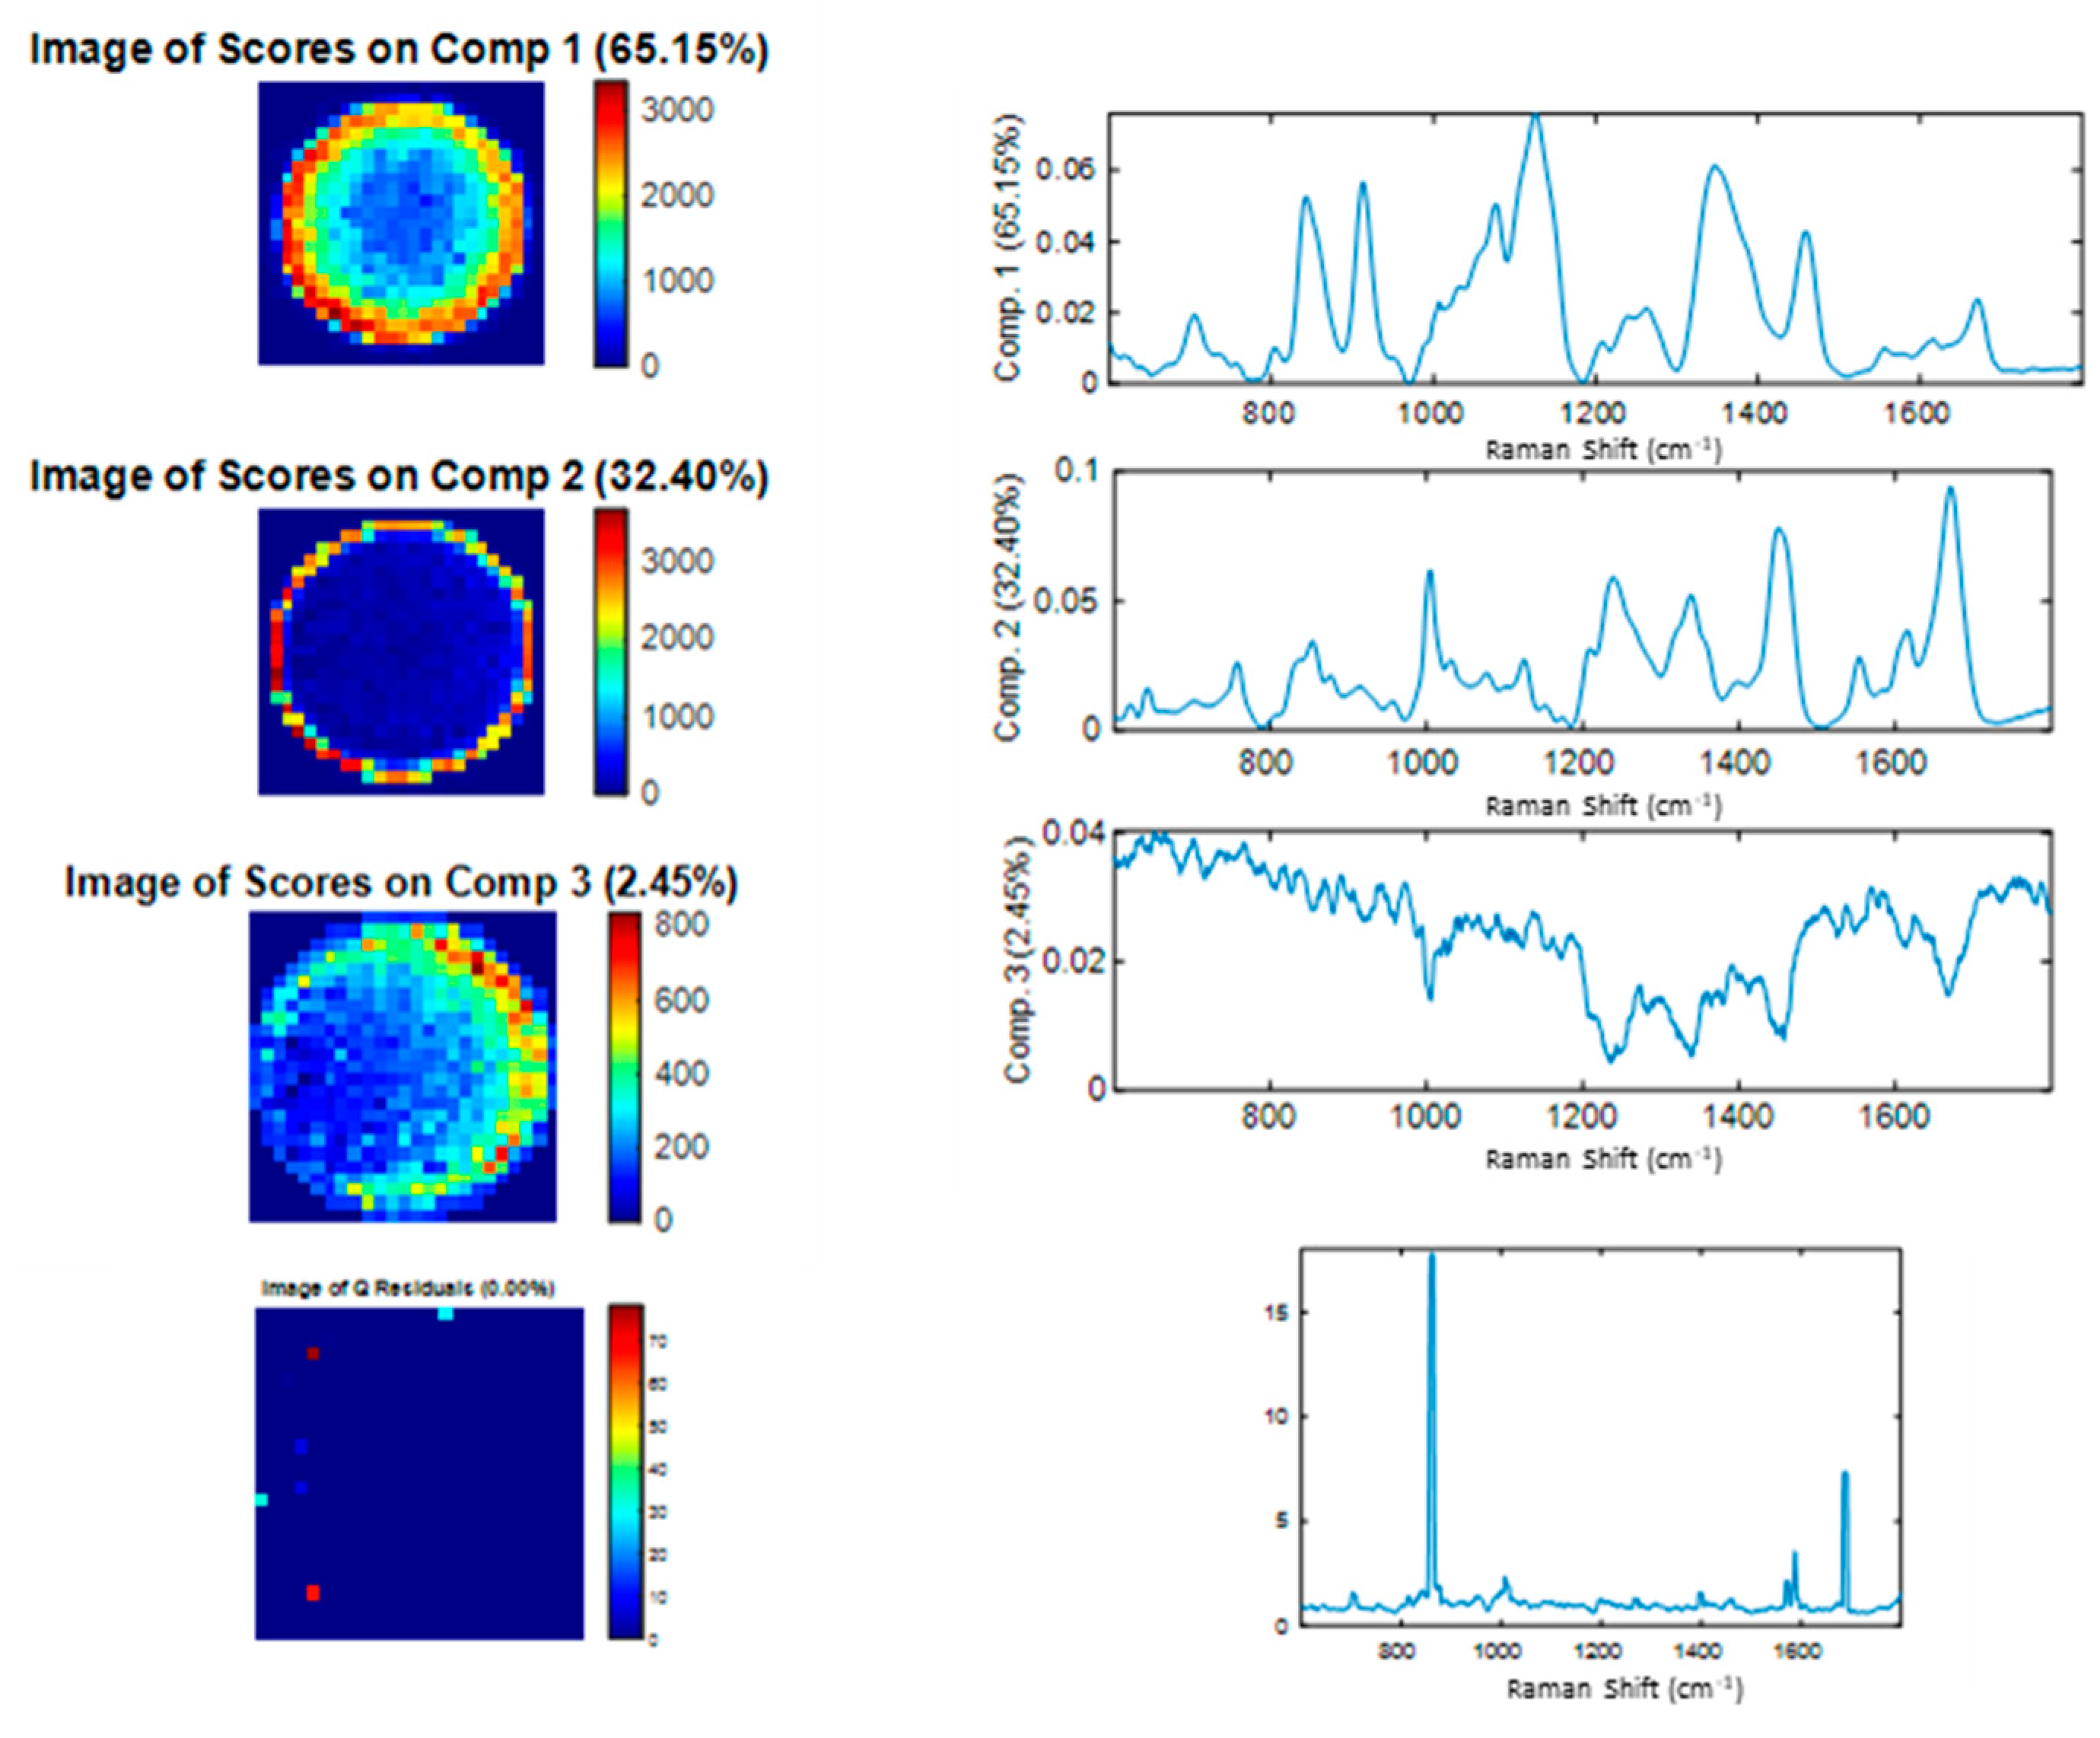

3.2. Spectral Characterization of Commercial mAbs Solutions by DCDR Imaging and MCR-ALS Analysis